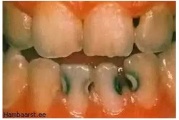

Vali sind huvitav pilt ja me näitame sellega seotud haigust ja sümptomeid